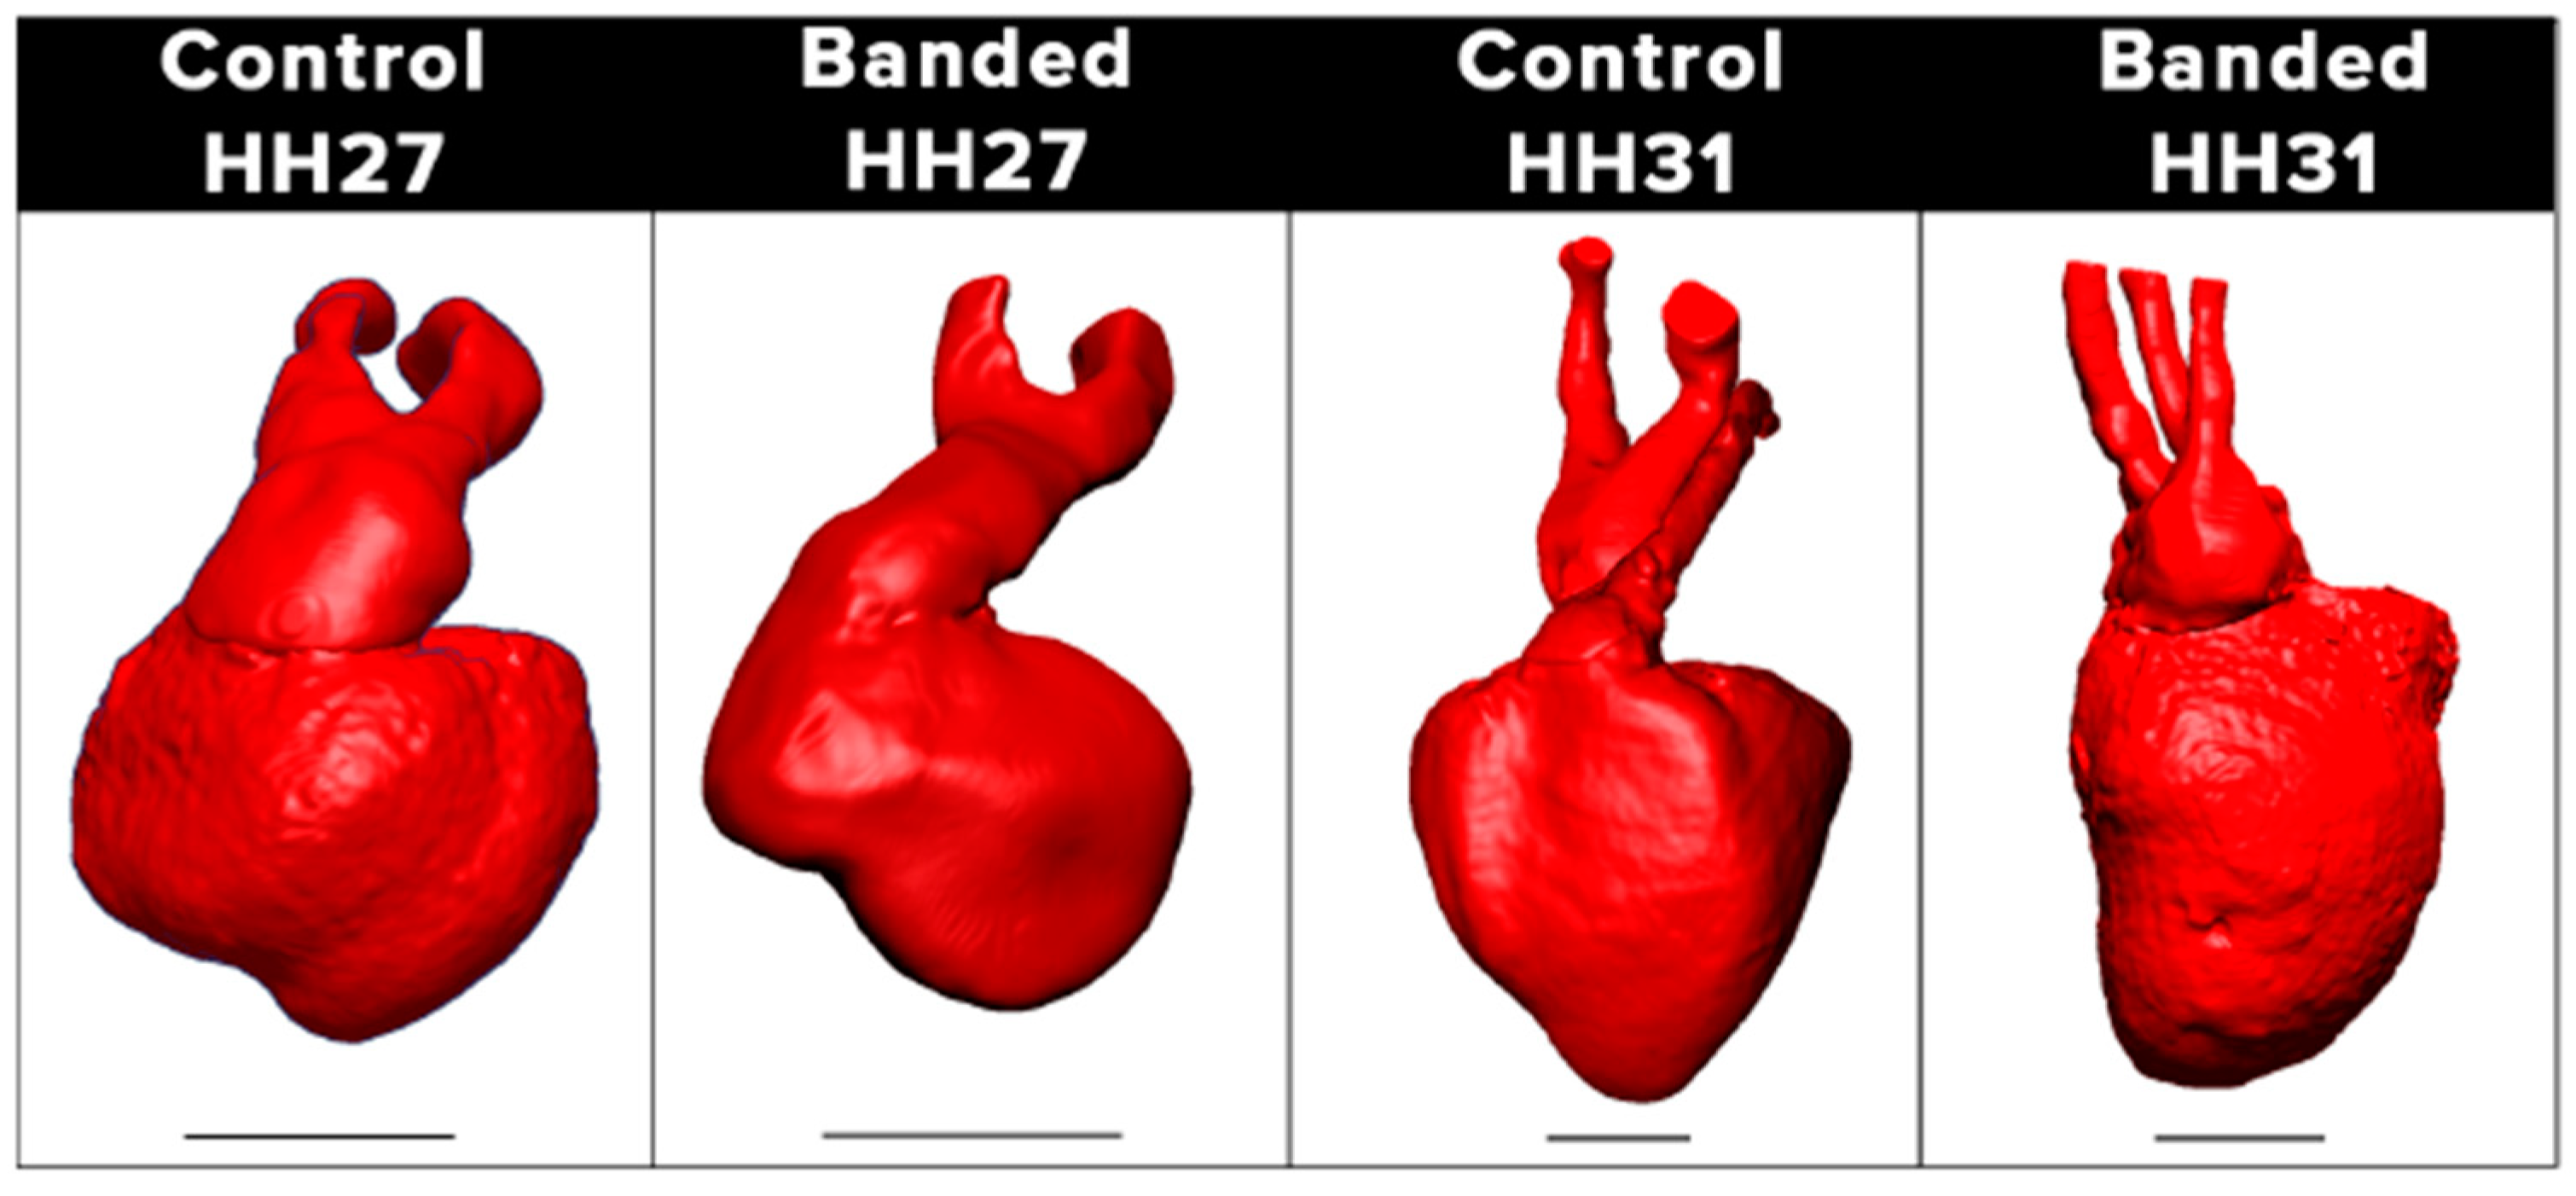

4.2. Hemodynamic Interventions in Avian Models

5.2. Ventricular Formation

5.3. Outflow Tract and Great Vessels